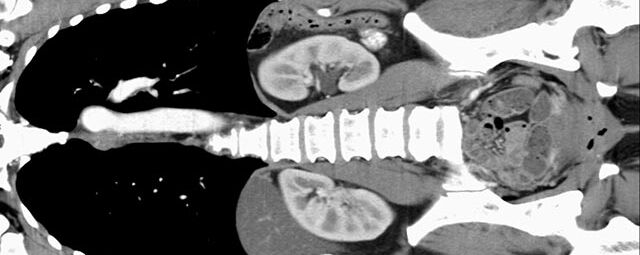

Abdomen (Bauch und Becken)

• Diagnostik von entzündlichen und tumorösen Erkrankungen der Bauchorgane

• Darstellung der großen Gefäße zur Erkennung von Gefäßverschlüssen (z. B. Mesenterial - Arterienembolie oder Einengungen von Gefäßen (z. B. Nierenarterien)

Wann muss Kontrastmittel eingesetzt werden?

In manchen Fällen – vor allem bei der Untersuchung von Hals, Thorax und Abdomen – reicht das Darstellungsvermögen des Gerätes allein nicht aus, deshalb werden kontraststeigernde Mittel, sog. Kontrastmittel, in das Blut (zum Darstellen oder Abgrenzen von Gefäßen oder auch zur Unterscheidung von gesundem und krankem Gewebe) oder auch zum Trinken (zur besseren Abgrenzung des Magen-Darm-Traktes) verabreicht.